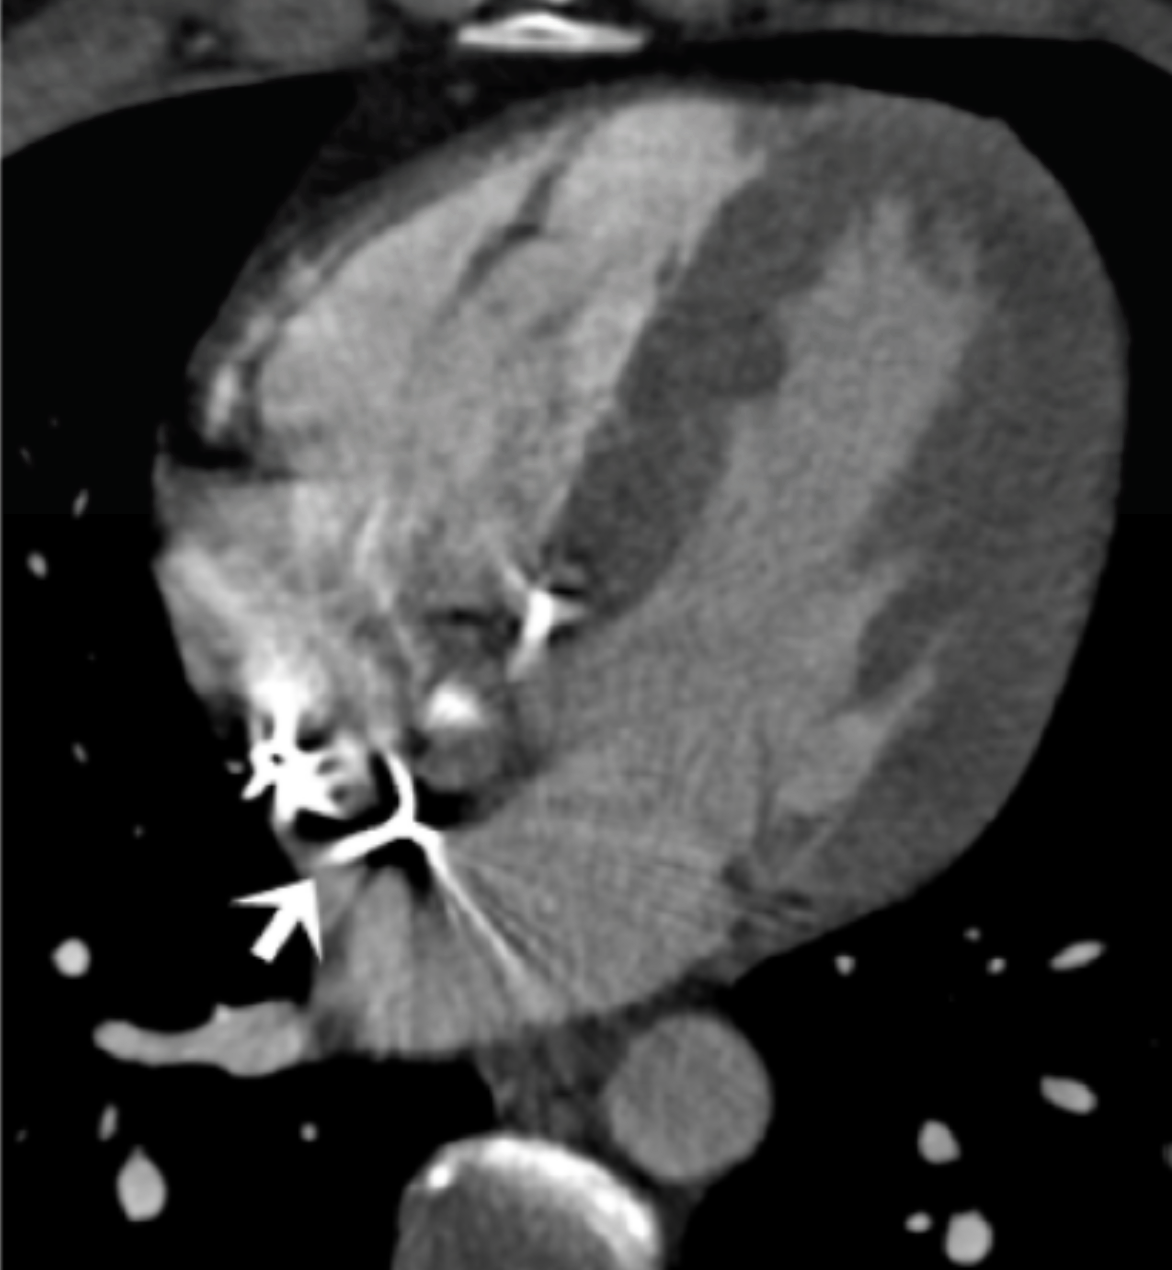

What is the arrow pointing at?

RV pacemaker leads - metal artifacts